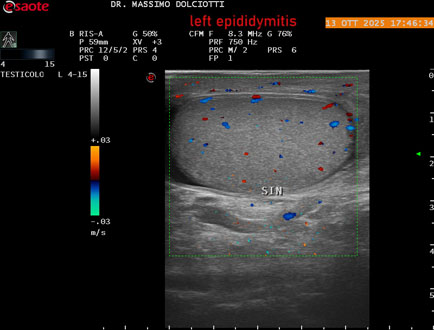

Data inserimento: 14/10/2025

Ecografia del: 13/10/2025

Strumento: Esaote MyLab Eight

Sonda: Lineare Multifrequenza 4-15 MHz

Età Paziente: M 70 anni

Motivazione dell'esame: da 2 giorni dolore al testicolo sinistro.

Commento all'esame: le immagini ed il video documentano l'epididimo sinistro spiccatamente aumentato di volume e di vascolarizzazione, come da flogosi. Didimo sinistro lievemente aumentato di volume. Quadro clinico ed ecografico da ricondurre ad epididimite acuta sinistra.

Conclusioni: epididimite acuta sinistra (acute left epididymitis).

Presentazione: Dr. Massimo Dolciotti - Ancona